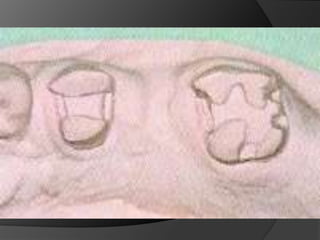

El objetivo básico de toda restauración cementada es estar bien adaptada y con una línea mínima de cementoTipos de Terminación cervical

HOMBRO O ESCALÓN: Es un tipo de terminación donde la pared axial de la preparación forma un ángulo de aproximadamente 90º con la pared cervical	Indicación: Coronas de porcelana pura o M/P con terminación V en porcelana	Contra:  Exige mayor desgasteDificulta el escurrimiento del cemento

HOMBRO O ESCALON BISELADO: Es un tipo de terminación en la que se da la formación de un ángulo de aprox. 90º entre las paredes axial y cervical, con biselado de la arista cavo-superficial. Biselado de 45ºIndicación: Coronas M/P en aleación semi o preciosa	Se disminuye el desajuste marginalFresa: Troncocónica de punta plana

CHAFLÁN:  Es un tipo de terminación donde la unión entre la pared axial y la gingival es hecha por un segmento de círculo, que deberá presentar un espesor suficiente para acomodar el metal y la porcelana. 	Considerada como la idealIndicaciones:  Coronas M/P en aleaciones básicas Fresa: Troncocónica de punta redondeada

CHANFERETE: Es un tipo de terminación en que la unión entre la pared axial y la gingival son hechas por un segmento de círculo de pequeña dimensión, debiendo presentar espesor suficiente para el metalIndicación: Caras palatinas, linguales y linguoproximales. Coronas parcialesFresa: Troncocónica de punta redondeada

FILO DE CUCHILLO: Es un tipo de terminación en la cual se desgasta la mínima cantidad de tejido posible aprox. 0,5 a 1 mm.	Indicación: Coronas solo metálicasFresa: Interproximal o de punta aguda

El objetivo básicode toda restauración cementada es estar bien adaptada y con una línea mínima de cementoTipos de Terminación cervical

HOMBRO O ESCALÓN:Es un tipo de terminación donde la pared axial de la preparación forma un ángulo de aproximadamente 90º con la pared cervical Indicación: Coronas de porcelana pura o M/P con terminación V en porcelana Contra: Exige mayor desgasteDificulta el escurrimiento del cemento

HOMBRO O ESCALONBISELADO: Es un tipo de terminación en la que se da la formación de un ángulo de aprox. 90º entre las paredes axial y cervical, con biselado de la arista cavo-superficial. Biselado de 45ºIndicación: Coronas M/P en aleación semi o preciosa Se disminuye el desajuste marginalFresa: Troncocónica de punta plana

CHAFLÁN: Esun tipo de terminación donde la unión entre la pared axial y la gingival es hecha por un segmento de círculo, que deberá presentar un espesor suficiente para acomodar el metal y la porcelana. Considerada como la idealIndicaciones: Coronas M/P en aleaciones básicas Fresa: Troncocónica de punta redondeada

CHANFERETE: Es untipo de terminación en que la unión entre la pared axial y la gingival son hechas por un segmento de círculo de pequeña dimensión, debiendo presentar espesor suficiente para el metalIndicación: Caras palatinas, linguales y linguoproximales. Coronas parcialesFresa: Troncocónica de punta redondeada

FILO DE CUCHILLO:Es un tipo de terminación en la cual se desgasta la mínima cantidad de tejido posible aprox. 0,5 a 1 mm. Indicación: Coronas solo metálicasFresa: Interproximal o de punta aguda